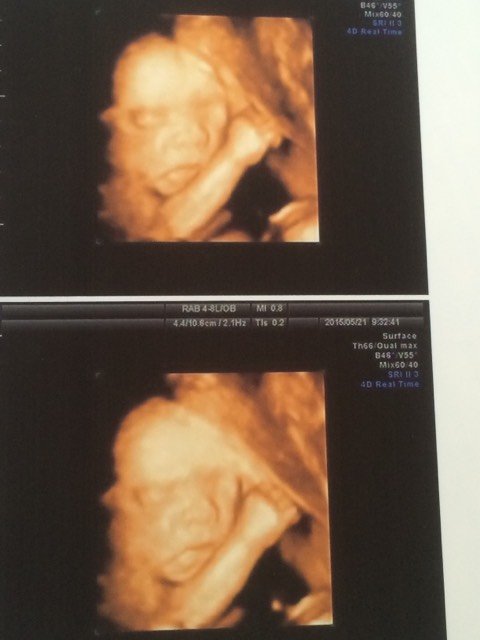

上午刚做的四维彩超,也不知道是男宝还是女宝,为什么看宝宝长得怎么那么丑

四维照出来看着都很丑的,生出来后长长就好了

彩超出来的照片都好丑的,因为他(她)泡在羊水里。宝妈一定会生个漂亮宝宝的